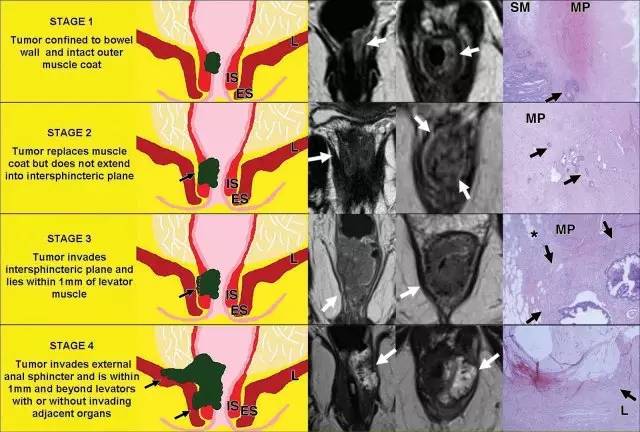

肛管直肠结合部,直肠固有肌层变化:1. 环形肌变厚形成内括约肌。2. 外括约肌复合体由肛提肌最下部,耻骨直肠肌和外括约肌组成。3. 低位肛管中两个括约肌形成明显的括约肌间隙。

低直肠肿瘤与阳性切缘率较高,局部复发率高,存活率差相关。这主要是由于解剖学考虑以及直肠系膜在此水平下降的事实。

有学者提出了一种低直肠肿瘤 T 分期。这种分期是基于冠状和轴向 T2 加权图像。

对于低直肠肿瘤,可以根据肿瘤分期进行三种不同的手术方式。